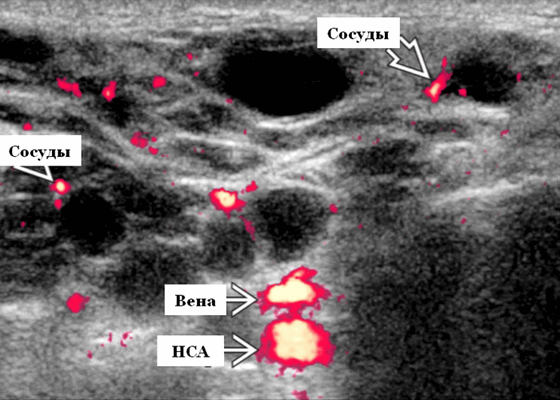

- Серошкальное УЗИ. Спектр сонографических находок от простых кист до смешанных и солидных образований. Кистозные, смешанные и солидные поражения могут возникать одновременно в околоушных железах. Кистозные поражения (кисты ДЛК). Хорошо очерченная киста, разного размера, от анэхогенной до гипоэхогенной структуры с задним акустическим усилением. Сеть тонких перегородок ± муральные узлы. Часто встречаются внутренние эхо, которые могут быть мобильными. Сотовидная внешность паренхимы околоушной железы, когда она диффузно изменена з а счет кист. Смешанные поражения (ДЛП). Границы могут быть плохо очерченными, разного размера. Структура преимущественно гипоэхогенная, железы могут быть неоднородными. Без заднего акустического усиления. Солидные поражения (околоушная лимфаденопатия). Множественные овальные / круглые, гипоэхогенные, внутрипаротидные лимфоузлы на УЗИ. Четкий корковый слой ± сохранная корневая архитектура. Сопутствующая реактивная шейная лимфаденопатия

- Цветной допплер. Кистозные поражения: от бессосудистого до умеренного сосудистого кровотока в перегородках, интрамуральных лимфоузлах и на периферии. Смешанные поражения: переменная, васкуляризация от легкой до умеренной. Солидные поражения: внутрипаротидная васкуляризация.